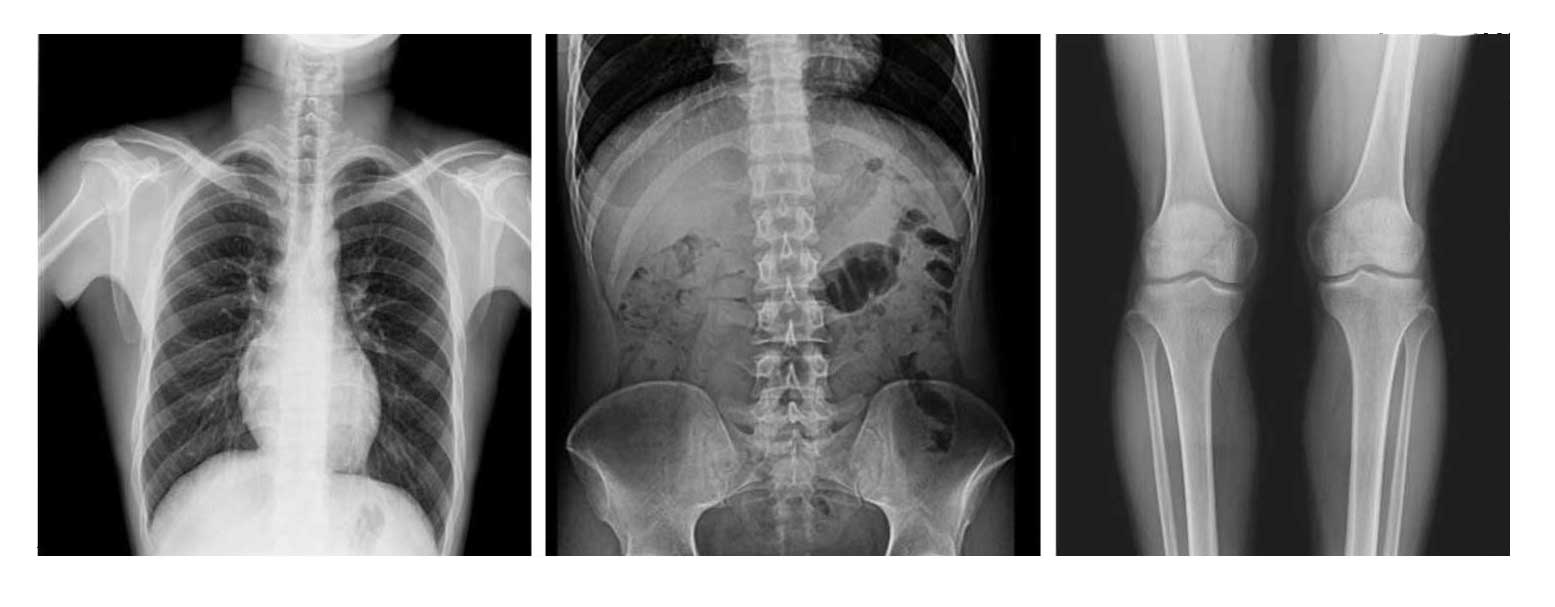

- Применяется для любых клинических рентгенологических исследований, включая специализированную позиционную рентгенографию.

- Автоматическая сшивка изображений (опция): формирование предоперационных планов и оценка послеоперационных результатов (сколиоз, нагрузка на ортопедические изделия, протезирование колена, эндопротезирование тазобедренного сустава).

Рентгенологические исследования: рентгенография больших переломов костей и масштабное физическое рентгенографическое обследование, флюороскопия всех частей тела (грудная клетка, живот и т.п.), пищеводная ангиография, ангиография верхних отделов желудочно-кишечного тракта, полная ангиография желудочно-кишечного тракта, оральная холецистография, внутривенная холангиография, Т-образная холангиография, ЭРХПГ, внутривенная пиелография, гистеросальпингография и т.д.